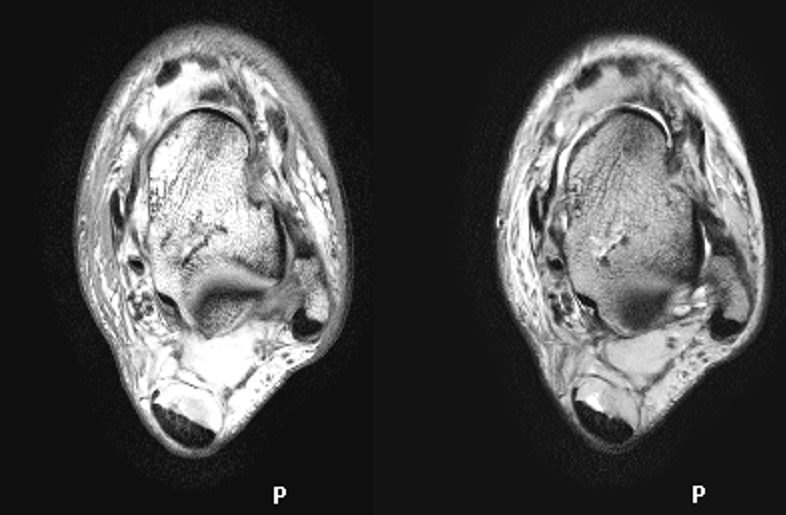

距骨骨软骨损伤

病因病理机制:

• 距骨骨软骨损伤(OLT)是经软骨的骨折、骨软骨骨折、剥离性骨软骨炎和距骨穹窿骨折的通称。

• 直接创伤或反复微创

• 骨坏死过程导致软骨下骨折和塌陷

• 累及关节软骨和软骨下骨内侧(60%)和外侧(40%)

MR表现:

MRI矢状面显示病变位于距骨圆顶最上缘,冠状面位于内侧角和外侧角。

四期:

Ⅰ期:软骨下骨小梁压缩

Ⅱ期:软骨下囊肿

Ⅲ期:不完全性碎片分离,无移位的碎片周围可见液体

Ⅳ期:碎片移位